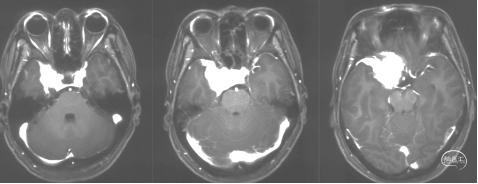

术前影像学检查

头颅MRI+增强